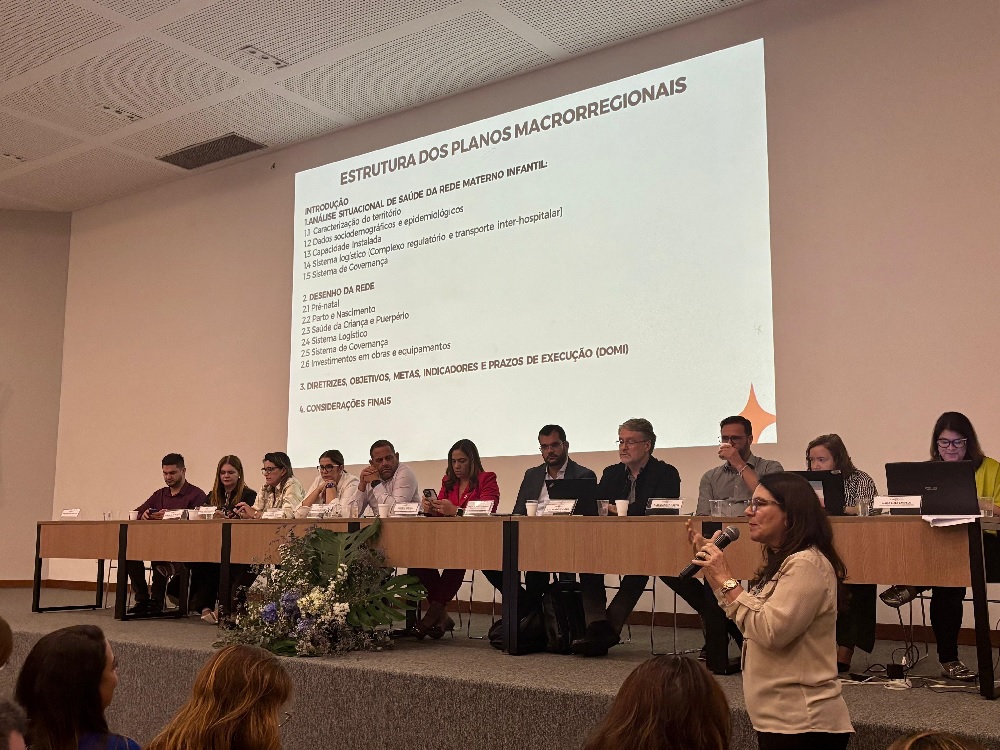

Bahia Geral Medicina Mulher Notícias Saúde

Em reunião da CIB, municípios e Estado formalizam a pactuação regional da Rede Alyne, fortalecendo a cooperação e a implementação das ações conjuntas

Por Redação * A 326ª Reunião Ordinária da Comissão Intergestores Bipartite (CIB), órgão colegiado responsável pelas decisões do Sistema Único …

Bahia Geral Medicina Mulher Notícias Saúde

Em reunião da CIB, municípios e Estado formalizam a pactuação regional da Rede Alyne, fortalecendo a cooperação e a implementação das ações conjuntas

Por Redação * A 326ª Reunião Ordinária da Comissão Intergestores Bipartite (CIB), órgão colegiado responsável …